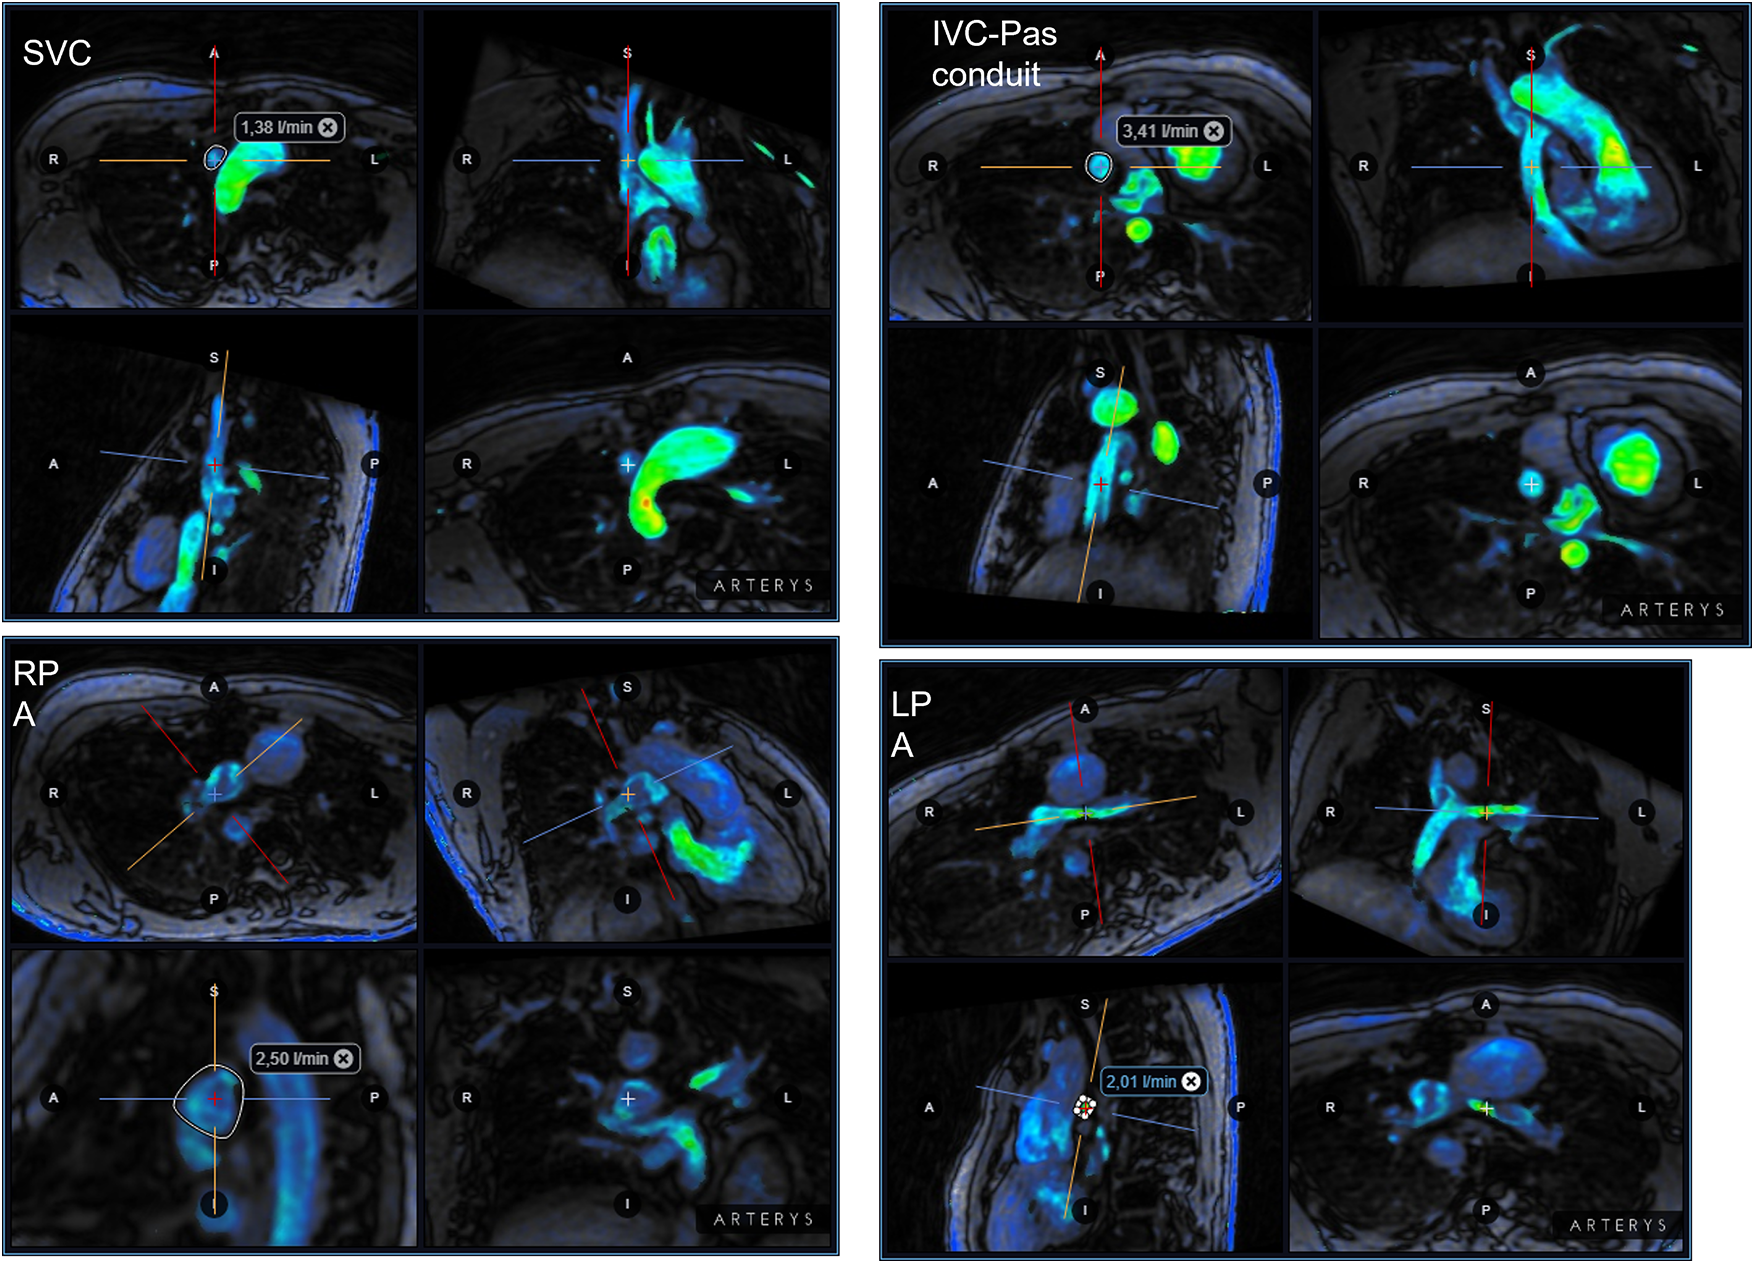

Briefly, functionally single-ventricle short axis was visualized from the base to the apex, using a cardiac cine balanced steady-state free-precession (SSFP) pulse sequence with the following parameters: retrospective ECG gating, field of view 340–360 mm, flip angle 35°–50°, TE 1.4–1.9 ms, TR 2.8–3.8 ms, slice thickness 6–8 mm, slice gap 0 mm, number of signal averages 1–3, reconstructed cardiac phases 30. Several 2D flow scans were performed to evaluate the blood flow in the ascending aorta (Ao), the superior vena cava (SVC), the right pulmonary artery (RPA) and left pulmonary artery (LPA), the individual right and left pulmonary veins (PVs) and the inferior vena cava-pulmonary arteries-conduit/tunnel (abbreviated in the following by IVC-PA conduit) (Fig. 1). The following parameters were used for 2D flow acquisitions: field of view 280–340 mm, flip angle 15°–20°, slice thickness 5–6 mm, view per segment 1–2, number of signal averages 2–4, velocity-encoding (VENC) values 100–450 cm/s depending on the expected blood velocity, reconstructed cardiac phases 30. All 2D flow scans were acquired during free-breathing. The MRI study was completed using a contrast-enhanced (gadopentetate dimeglumine 0.2–0.4 ml/kg). MR angiographic sequence or a time-resolved angiography for the anatomic evaluation of the Fontan pathway. In patients aged <8 years or with incapacity to collaborate the CMR exam was performed on deep sedation using titrated propofol.

images

Figure 1: Schematic illustration of multiple 2D flow prescriptions. IVC, inferior vena cava; LPA, left pulmonary artery; RPA, right pulmonary artery; PA, pulmonary arteries; PVs, pulmonary veins; SVC, superior vena cava

A 4D flow MRI sequence was also prescribed in axial or coronal orientation covering the entire thorax with the following parameters: field of view 250–400 mm, flip angle 8°–15°, TR 3.8–5.3 ms, TE 2.0–3.2 ms, slice thickness 2.2–3.0 mm, in-plane resolution 1.9–3.1 mm, view per segment 1–4, number of signal averages 1–4, VENC 70–150 cm/s, reconstructed cardiac phases 20–32, acquisition time 5–12 min. The SSFP and 2D flow images were elaborated by means of a commercially available software (Mass plus and CV Flow, respectively; version 4.0, MR Analytical Software Systems, Leiden, The Netherlands). Ventricular volumes, mass (indexed to body surface area) and the ejection fraction were calculated. 4D flow MRI data were processed using Arterys Cardio AIMR (Arterys Inc., San Francisco, CA). Examples of the 4D flow MRI are illustrated in Fig. 2 and Supplementary Movie S1.

Figure 2: Examples of 4D flow MRI of the IVC-PA conduit in the same patient of Fig. 1. IVC, inferior vena cava; LPA, left pulmonary artery; RPA, right pulmonary artery; PA, pulmonary arteries; PVs, pulmonary veins; SVC, superior vena cava